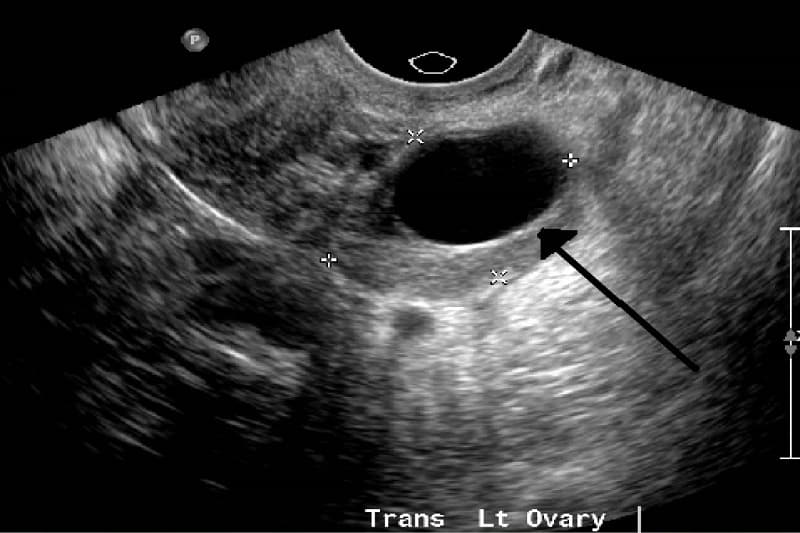

U nang buồng trứng echo trống là một dạng u nang lành tính thường gặp ở phụ nữ. Echo buồng trứng là âm thanh dội lại từ các khối hoặc vùng trong buồng trứng khi siêu âm. U nang echo trống, hay nang buồng trứng echo âm, là dạng nang đặc biệt không tạo tiếng vang khi siêu âm. Nó có thể là dấu hiệu của u nang buồng trứng như u nang cơ năng (hoàng thể, hoàng tuyến, noãn) hoặc u nang thực thể (u quái, u nang nước, u nang nhầy).

Đặc điểm của nang buồng trứng echo trống: Kích thước có thể dao động từ vài mm đến vài cm và vị trí thường nằm ở một trong hai buồng trứng.

Các chị em phát hiện ra nang buồng trứng echo trống chủ yếu qua siêu âm.

U nang buồng trứng khối echo trống thường được chẩn đoán bằng siêu âm. Trong một số trường hợp, bác sĩ có thể yêu cầu các xét nghiệm khác, chẳng hạn như xét nghiệm máu hoặc chụp CT.